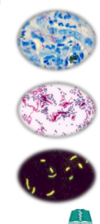

What is the advantage os using a flourescent stain versus a non-fluourescent stain?

the fluorescent stain allows the lab to identify organisms that are present in lower quantities

the fluorescent stain allows the technologist to “pick out” organisms from a clinical matrix

What are the 2 methods to the direct exam “Smear” test? What are benefits to each? what are the major drawbacks?

- Acid-Fast

- cheap, easy

- Ziehl-Neelson/Kinyoun stain

- carbol fischin (heat or phenol to increase uptake)

- decolorize

- methylene blue or brilliant greeen

- carbol fischin (heat or phenol to increase uptake)

- Auramine-Rhodamine (fluourescent)

- binds acid fast cell wall

- more sensitive, still fairly cheap

- requires fluourescent microscope

major drawbacks: specificity…species specific morphology. You know it is mycobacterium, but not necessarily mycobacterium tuberculosis